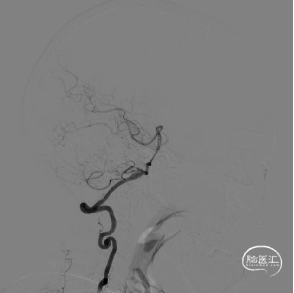

术前DSA评估:

主动脉弓弓型:II型弓。

前循环造影显示双侧颈内动脉迂曲。

双侧椎动脉迂曲,右椎动脉优势,右侧椎动脉V4段梭形动脉瘤,左椎PICA小动脉瘤。

3D重建,测量远端血管直径为2.71mm,近端血管直径为3.13mm,动脉瘤直径为9.80mm*13.18mm。

右侧颈内动脉及右侧椎动脉无明显异常。

左侧椎动脉V3段夹层改变。

左侧颈内动脉C3-C4段长段瘤样扩张。

多角度精确测量动脉瘤及病变区域,远端血管直径4.20mm,近端直径4.52mm,动脉瘤呈不规则形状,密网支架预计覆盖长度为56.44mm。